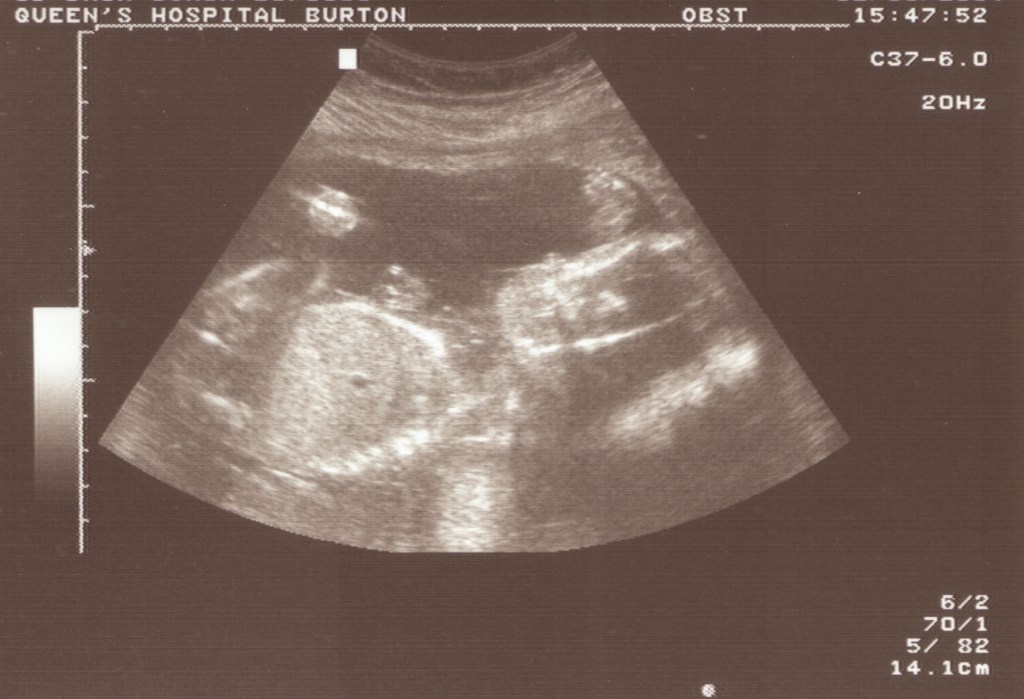

Arun Akash Dhir was born at 7am, on a crisp March morning, in Burton-Upon-Trent.